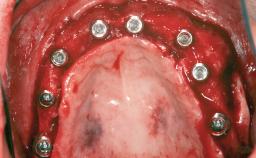

Ridge Preservation and Implant Placement for a Fixed Dental Prosthesis After a Car Accident

| # of Teeth | 6 |

| # of Implants | 4 |

| Type of Implants | One-Piece|Reduced-Diameter |